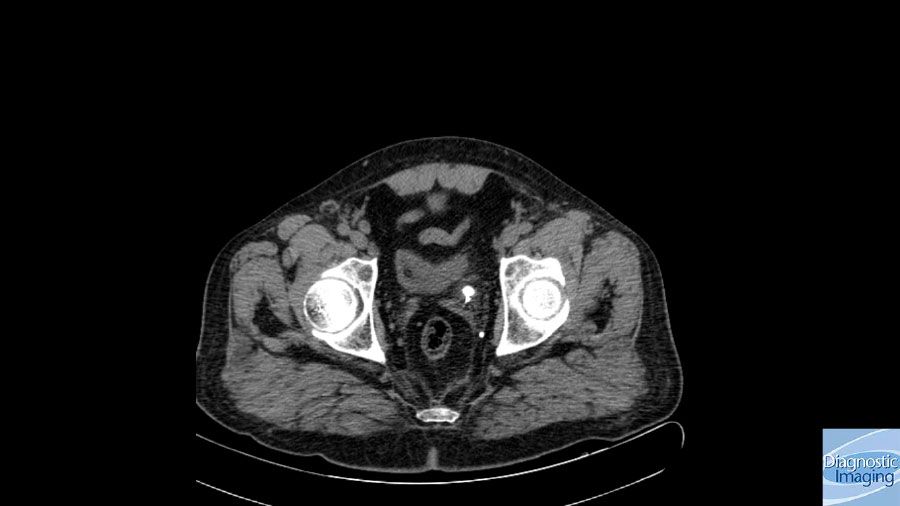

Case History: 50-year-old patient with ureteral stent evaluated with CT.